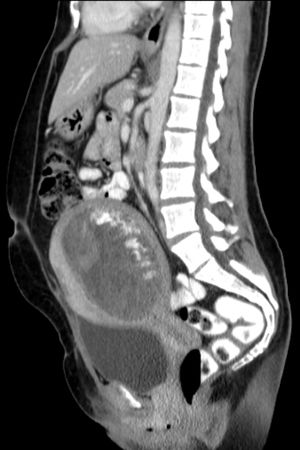

Hydatidiform mole on CT, sagittal view

Hydatidiform mole on CT, axial view

أما كيف يشخص الحمل العنقودي ، فعن طريق إجراء تحاليل لمعرفة نسبة هرمون الحمل التي غالباً ما تكون عالية جداً بالمقارنة مع الحمل الطبيعي• وهناك طريقة أخرى ، وهي إجراء الفحص بالأشعة الصوتية ، بحيث يكون مايشبه العاصفة الثلجية ، وهذا يدل على أن المشيمة غير طبيعية ، وإذا وجدت جنين فهذا قد يدل على أنه حمل عنقودي جزئي وعادة ما يكون الجنين غير طبيعي ويتوفى داخل الرحم في الأشهر الأولى من الحمل •